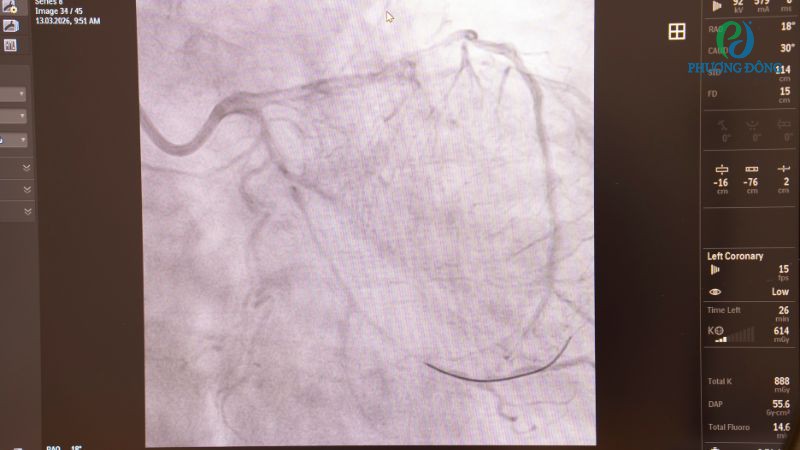

- Trung tâm sở hữu máy chụp mạch số hoá nền DSA Azurion 5 chuyên biệt, hỗ trợ bác sĩ quan sát rõ nét hệ thống mạch máu theo thời gian thực, từ đó tối ưu hiệu quả can thiệp vấn đề bất thường tại mạch vành, mạch não và mạch ngoại biên.

Quy trình can thiệp đặt stent tại Bệnh viện Đa khoa Phương Đông luôn được theo dõi, kiểm soát chặt chẽ nhờ ứng dụng công nghệ hiện đại. Qua đó tối ưu tiên lượng hồi phục hậu can thiệp, thực tế cũng ghi nhận nhiều bệnh nhân tỉnh táo, lấy lại sức khoẻ nhanh chóng và ổn định ngay khi trở lại phòng nội trú.